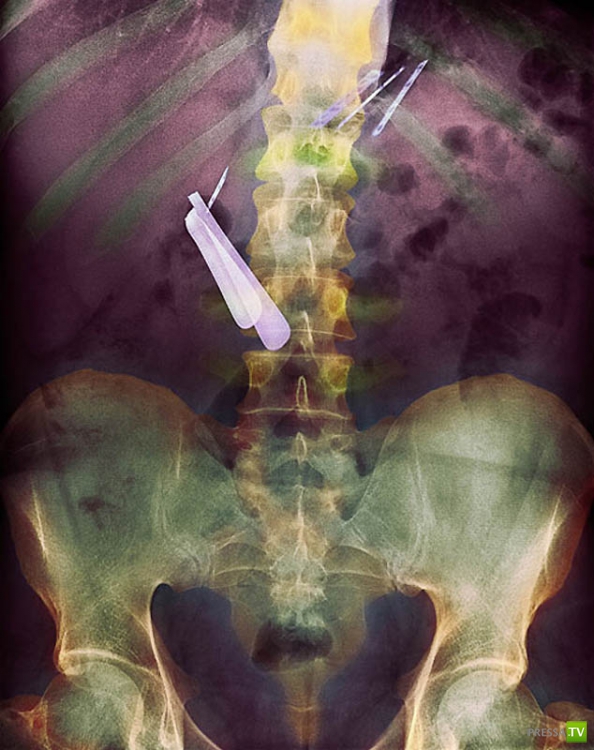

Цветной рентген желудка пациента, который проглотил бритву (по центру слева) и лезвия (вверху справа).